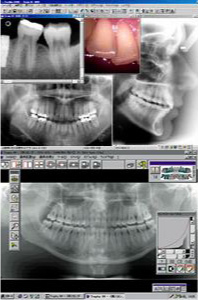

デジタルレントゲン

当クリニックでは従来型フィルムレントゲンに比較して放射線被爆線量が少ないデジタルレントゲン院内LANシステムを導入しております。これは従来型レントゲンと比較して1/10~1/4の線量で各種のレントゲン撮影が可能となりさらに薬剤等での現像処理などが必要なくなり、すぐにコンピューターで映像を読み込むので時間的にもスピーディーでまた眼の悪い患者様にもより分かりやすいように大きなモニターでご自身の歯の状態をご覧になれるというものです。

詳しく見たいところはさらに倍率をあげて診ることが出来ることから詳細の診断が飛躍的に向上し患者様にも我々医療従事者にも優しいレントゲンシステムと言えるでしょう。